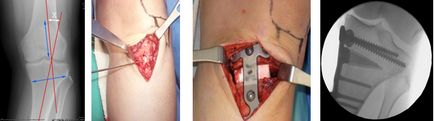

Javítás Az alsó végtag, amikor varus deformitás tengelyen tányérok

Csontösszekötő lemezek.

Ami a jövőt illeti, azt mondjuk, hogy a fő és szinte az egyetlen előnye, hogy a lapok, hogy nem látható kívülről. Annak ellenére, hogy a deformáció korrekciójára művelet külföldön használják elég gyakran, hogy van egy csomó hiányosságok, korlátozások és komplikációk. Önmagában a művelet meglehetősen összetett és traumatikus, azaz elvégzésére oszteotómián és rögzítésen igényel nagy metszést.

Szakaszai korrekciós osteotomiával és oszteoszintézisíemez

Ezt nevezhetjük komplikációk, mint a törés a sípcsont; peroneal idegkárosodás; suppuration üzemelnek; túlkorrekció vagy fordítva, nem megfelelő korrekció; instabil fixálás és másodlagos elmozdulás; mélyvénás trombózis, és így tovább.

Szövődményei osteosynthesis lemezek

Ezen túlmenően, a lemez nem biztosít stabil rögzítés. A műtét után, azt javasoljuk, egy megszorító rendszer 2-3 hónapig. Emiatt, próbáld meg nem működik mindkét lábát. Így a helyes mindkét lába van szükség két művelet időközönként néhány hónap. Tekintettel arra, hogy a lemezek el kell távolítani, beszélünk, legalább három műveleteket. Komoly korlátozások a korrekció mértékének (általában nem több, mint 12 fok), lehetetlen, hogy egyszerre korrigálja a varus (valgus) deformitást és meghosszabbítsák a végtag, valamint szükség esetén további korrekciós elemek (medialization, forgatás, stb.) Jelentős hátránya, hogy az alak a lábak a műtét után már nem lehetséges, hogy valahogy változtatni, vagy „csípés”. Lehetséges túlkorrekció, vagy éppen ellenkezőleg, nem a korrekció, aszimmetria a két láb korrekció.